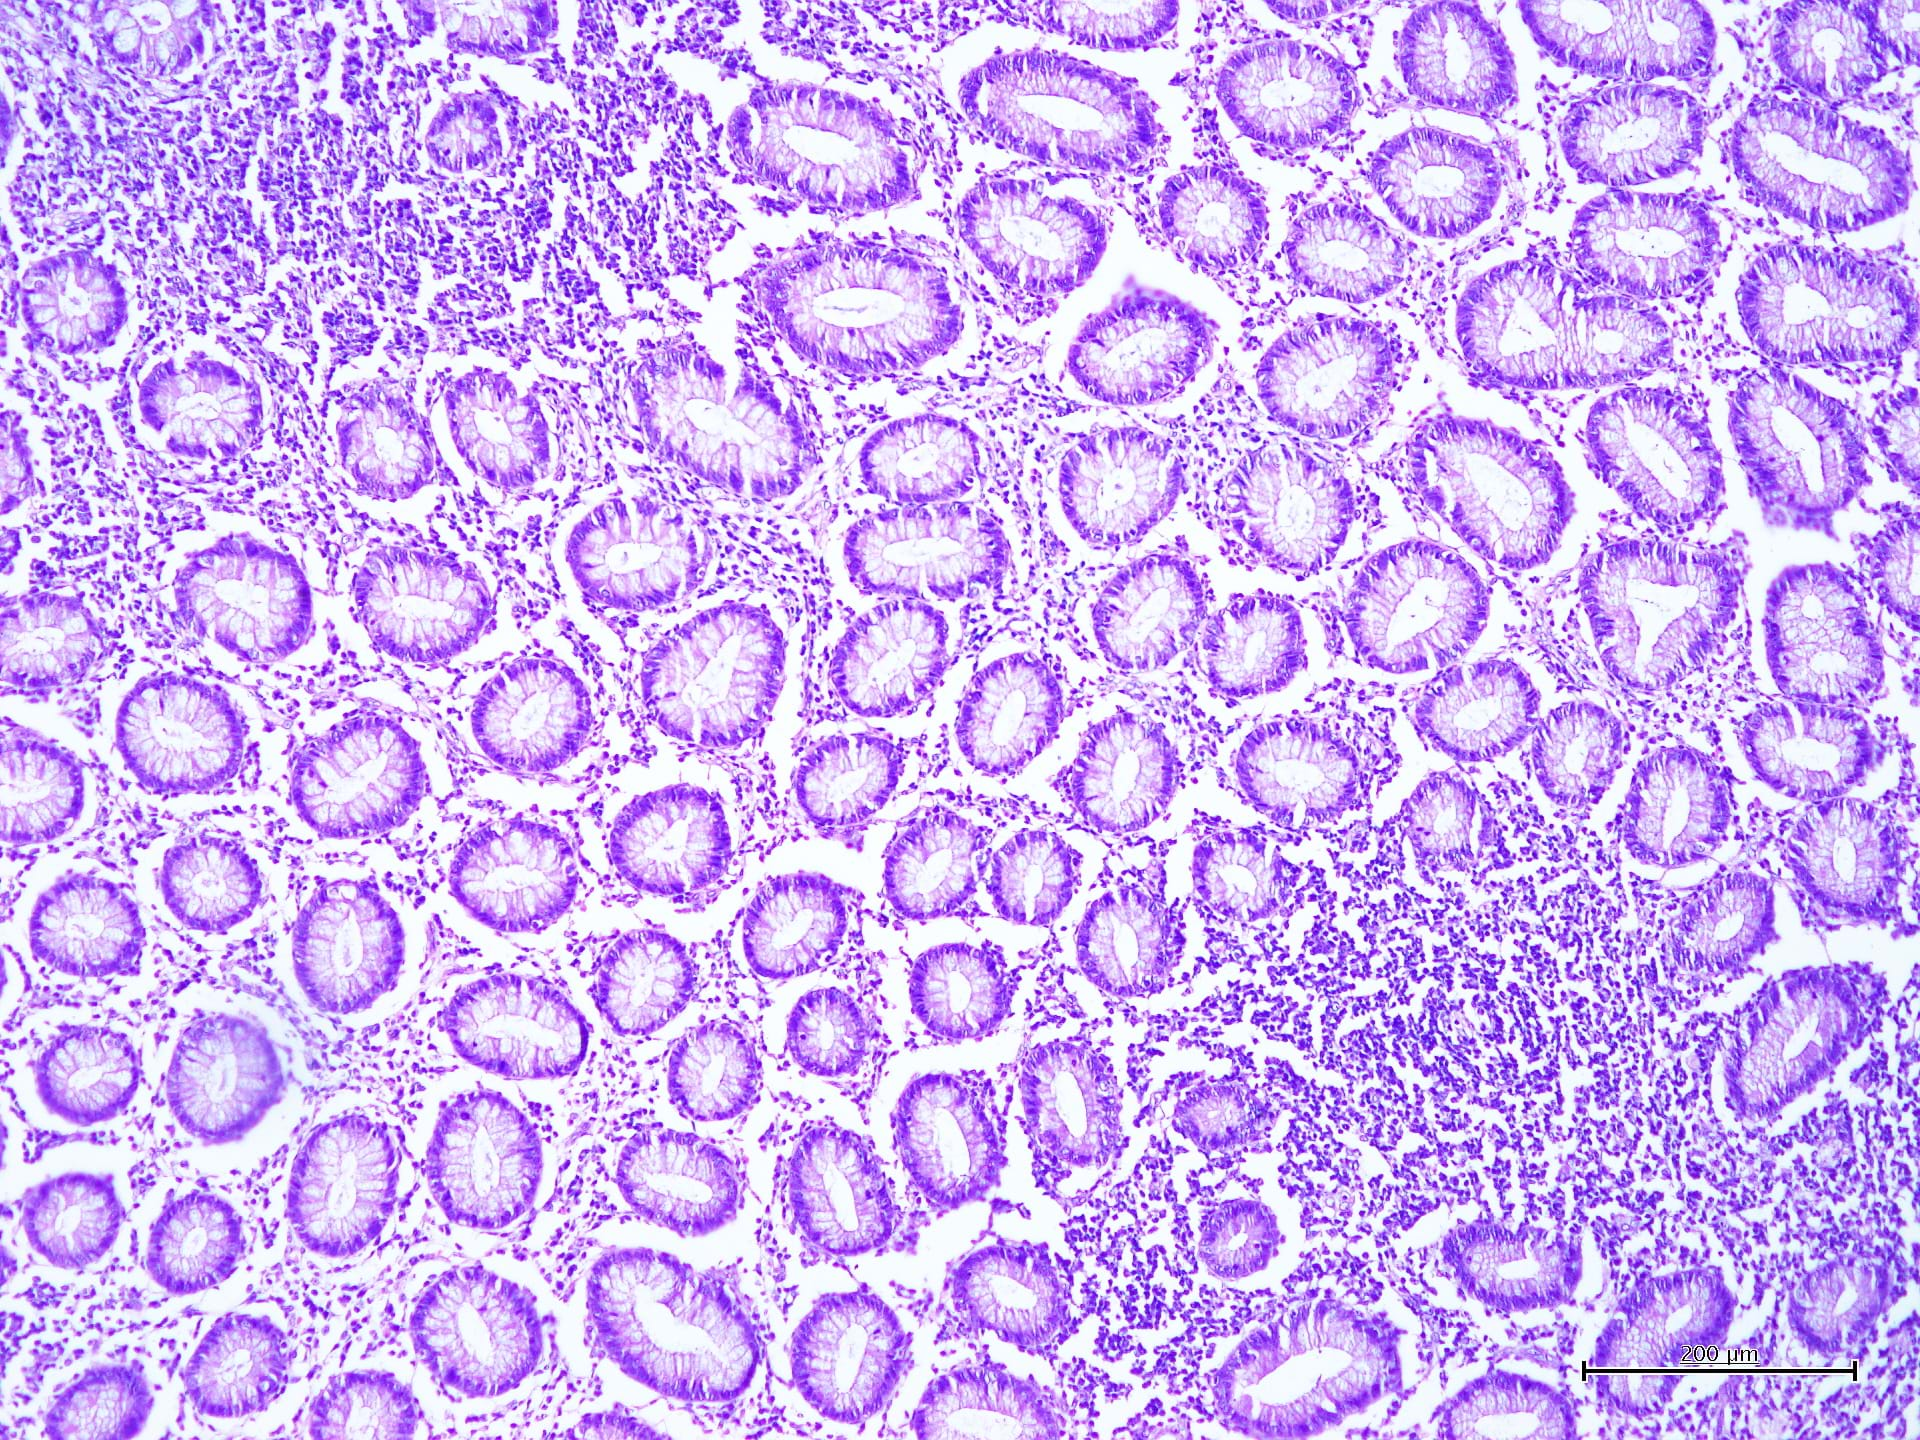

La colorazione Ematossilina – Eosina (H&E) è la colorazione più antica e più utilizzata nei laboratori di Anatomia Patologica di importanza essenziale per la diagnosi ancora oggi. Per questo motivo Diapath S.p.A. offre una gamma di coloranti, sviluppata secondo la letteratura di riferimento ed ottimizzata nell’ottica del costante miglioramento dei prodotti, consentendo di usufruire di eccellenti risultati, valorizzando dettagli nucleari ed enfatizzando gradazioni di intensità delle colorazioni citoplasmatica.

La colorazione Papanicolaou è una colorazione policroma per campioni citologici (sia di provenienza ginecologica che non ginecologica). Il metodo si basa su una colorazione nucleare a base acquosa e su due colorazioni citoplasmatiche a base alcolica. L'ematossilina viene normalmente utilizzata per la colorazione blu-violacea dei nuclei, OG6 e EA50 come coloranti del citoplasma. OG6 è la soluzione colorante che evidenzia il citoplasma nelle cellule e aree cheratinizzate. EA50 è una soluzione policroma che consente la differenziazione specifica dei citoplasmi delle cellule squamose epiteliali.